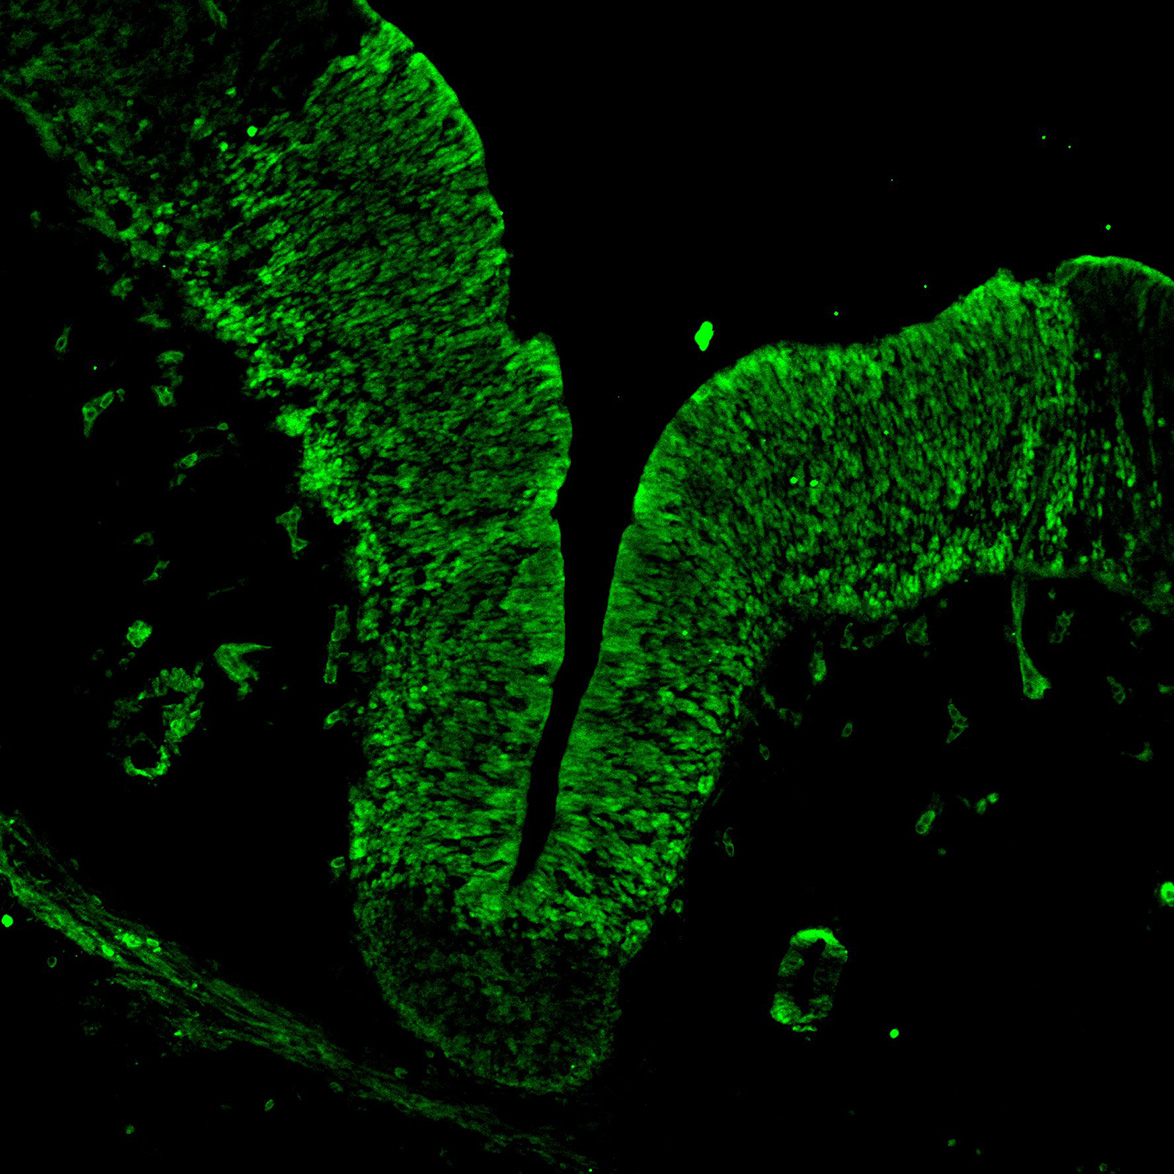

KI67

6PCW human midbrain